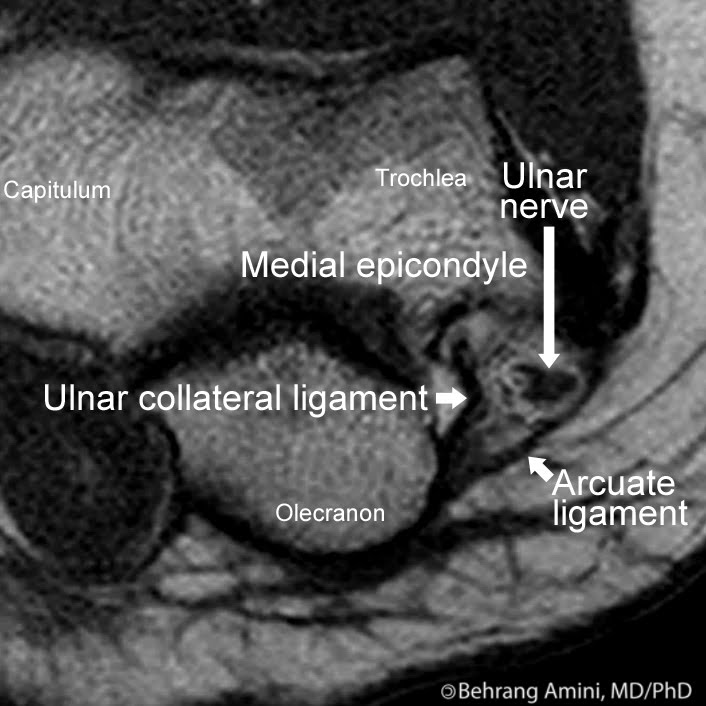

UCSD Musculoskeletal Radiology Cubital Tunnel X Ray Positioning cubital tunnel syndrome (cuts) is the compression of the ulnar nerve as it courses through the cubital tunnel. the cubital tunnel is a space through which the ulnar nerve passes posterior to the medial epicondyle of the. cubital tunnel syndrome is neuropathy of the ulnar nerve causing symptoms of numbness and shooting pain along the medial aspect. Cubital Tunnel X Ray Positioning.